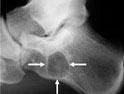

軟骨瘤為常見(jiàn)的良性骨腫瘤,內(nèi)生(髓腔性)軟骨瘤是指發(fā)生在髓腔內(nèi)的軟骨瘤,最為常見(jiàn);骨膜下(皮質(zhì)旁)軟骨瘤則較少見(jiàn)。軟骨瘤合并多發(fā)性血管瘤者稱馬弗西(Maffuci)綜合征。軟骨瘤單發(fā)多見(jiàn),多發(fā)較少見(jiàn),并具有對(duì)稱生長(zhǎng)的特點(diǎn),同時(shí)合并肢體發(fā)育畸形,又稱內(nèi)生軟骨瘤病;其發(fā)生于一側(cè)肢體者又稱歐利(Ollier)病。位于盆骨、胸骨、肋骨、四肢長(zhǎng)骨或椎骨的軟骨瘤易惡變;發(fā)生在指(趾)骨的軟骨瘤極少惡變。